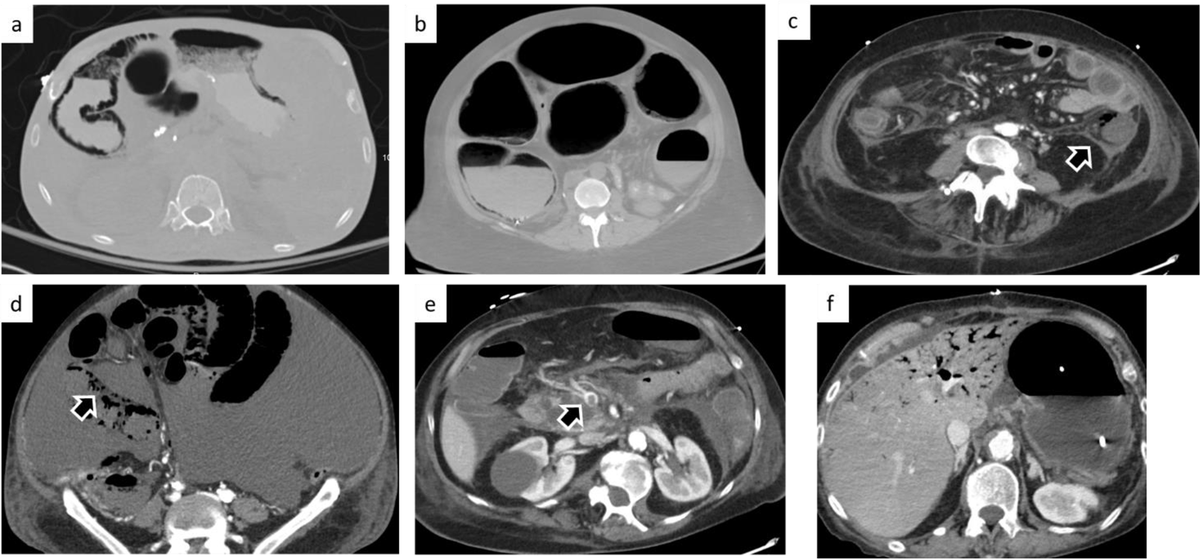

Excited to share our new paper in Abdominal Radiology ! We studied 313 pts with pneumatosis intestinalis on CT to better predict which cases indicate bowel ischemia. By combining clinical & radiological features, we achieved 85% AUC in identifying bowel ischemia. Francesca Rigiroli MD Alexander Brook

Our study showed that a model with radiological and clinical features: gas in the mesenteric and portal vein, fat stranding, age, WBC, creatinine, distention, rebound or guarding and shock can successfully identify patients with pathologic pneumatosis intestinalis.